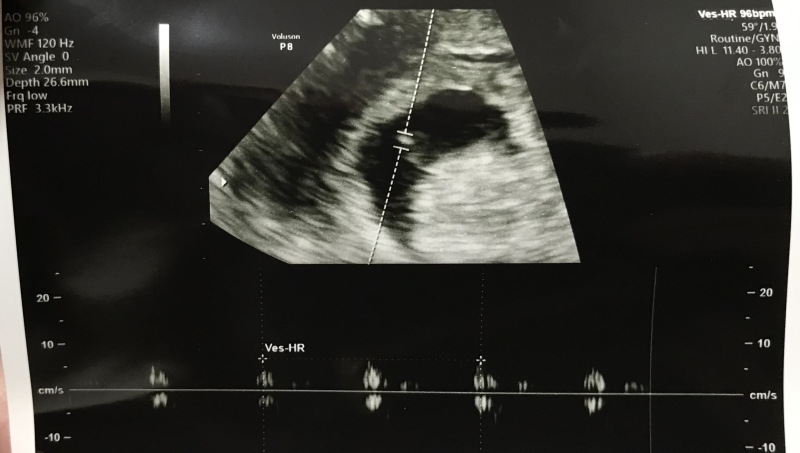

本日エコーをすると、CRL(胎芽?)が3.4㎜で卵黄嚢はっきり確認。心拍もわずかに確認出来ました。

エコーでは子宮には出血が確認できない。 今は出血があったり、流産しても染色体異常で出来ることはない。次は10日後に、とだけ言われました。